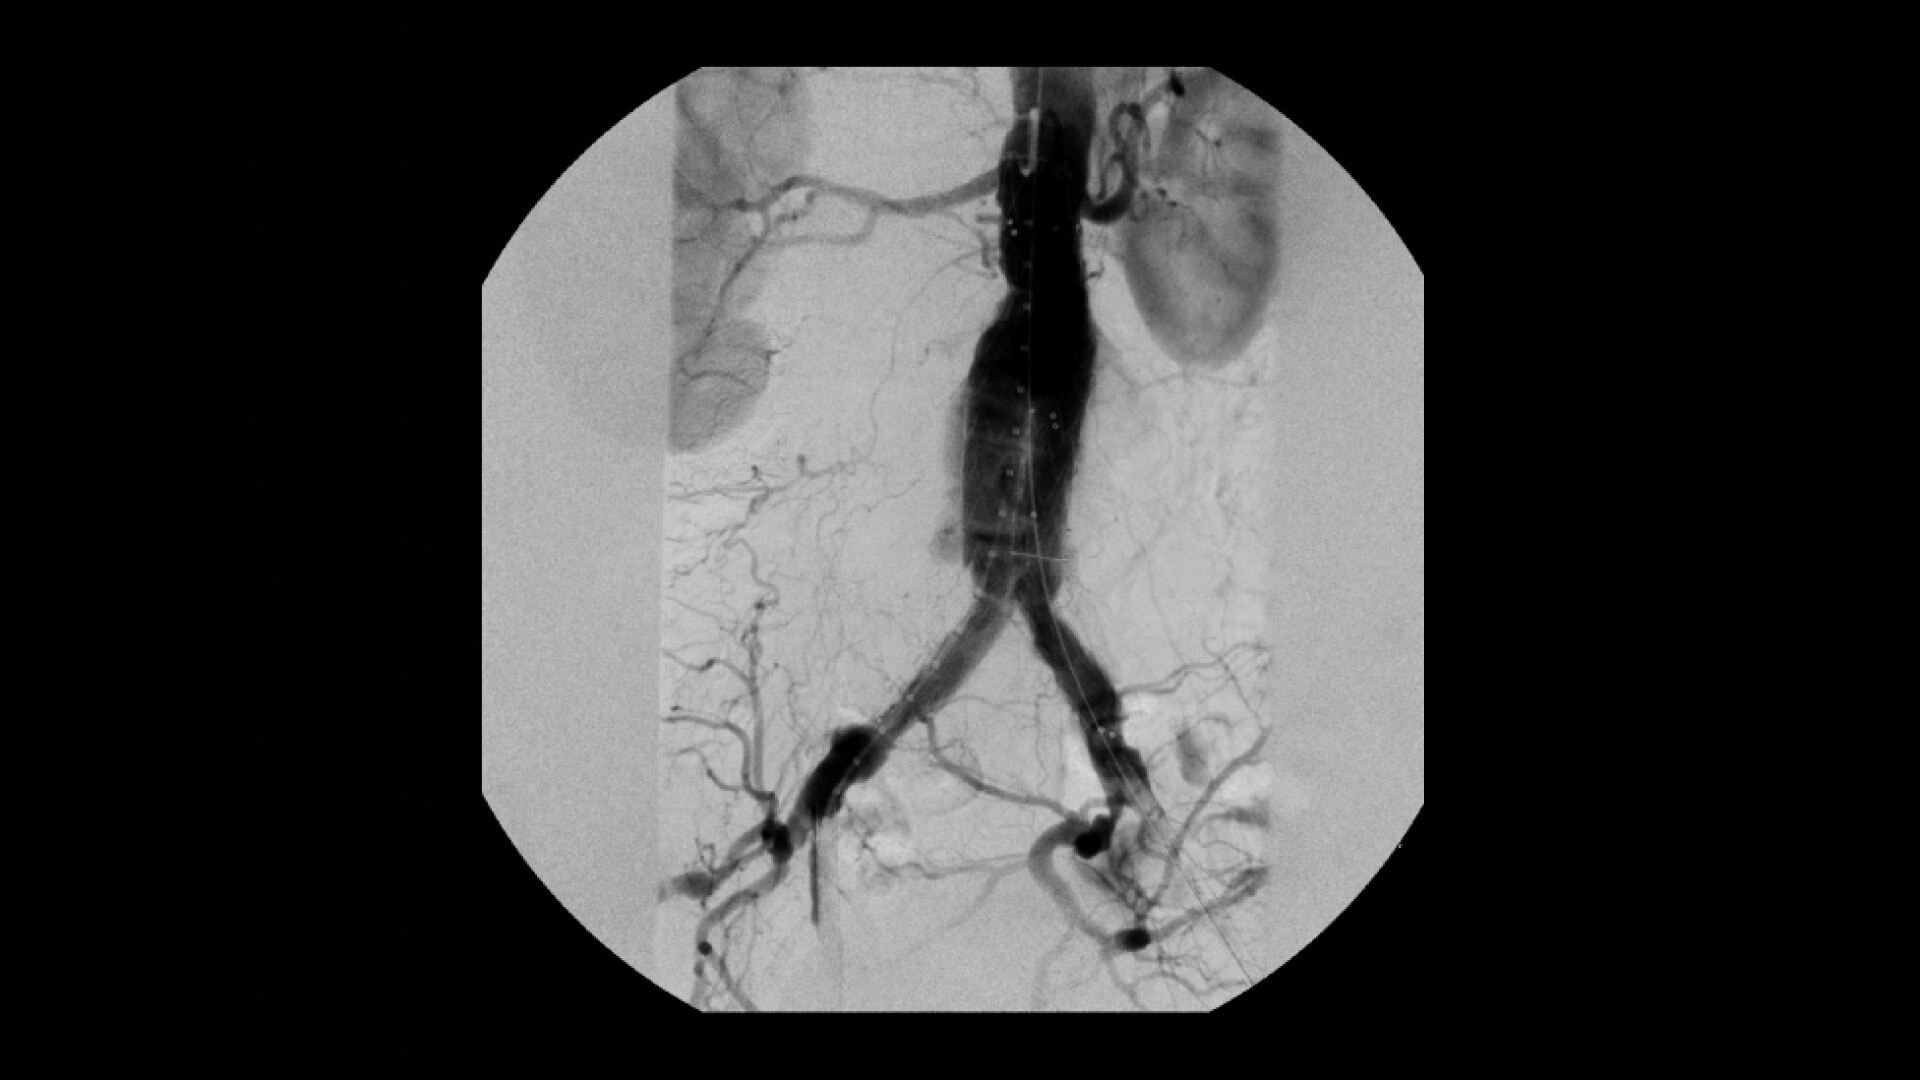

OEC C-arms are used by interventionalists and surgeons to obtain vascular imaging during peripheral to contrast run-off procedures. Superb resolution, even in the presence of motion, enables easy identification of anatomical landmarks and the extremity of the catheter, even as catheter tip moves.

Perform a full leg Bolus Chase in one contrast run with a Preset Profile that includes Motion Tolerant Subtraction, that dynamically adjusts image quality based on presence of motion.

During contrast run-off procedures, easily select contrast type with positive (e.g. Iodine) or negative (e.g. Carbon Dioxide) during subtraction. The OEC Elite CFD cardiovascular package also includes Roadmapping.

Complex vascular procedures require powerful imaging systems. OEC premium C-arms perform in a variety of procedures such as:

•Abdominal aortic aneurysm (AAA) stent and balloon deployment

• Infrarenal aortic aneurysm repair

• Recanalization and stent placement in iliac arteries

• Vascular long lesion treatment